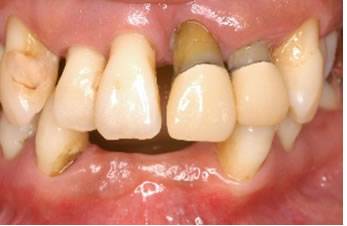

症例2

治療の特徴(患者Y様)

初診 2016年5月17日 / 経過 2018年7月2日

| 治療期間 | 2年2カ月 |

|---|---|

| 費用 | 保険内治療 |

| オペ費用 | 1ブロック約9,000円(3割負担) |

| 治療のデメリット | 歯内退縮が見られる。知覚過敏の症状が出ることがある。 |